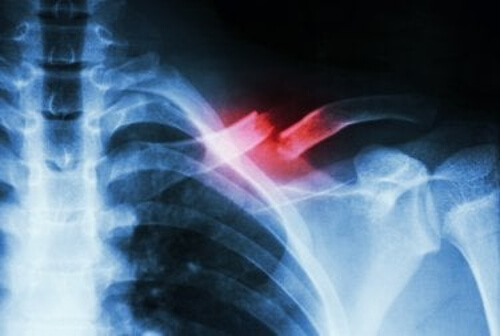

Złamanie kości

W wyniku przeciążenia w trakcie aktywności fizycznej może wystąpić tzw. złamanie naprężeniowe.